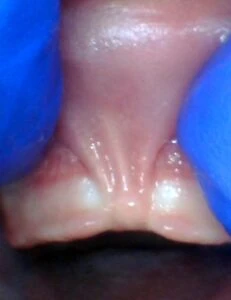

IMAGES OF TONGUE- AND LIP-TIES

Spectrum of lip restriction in an infant